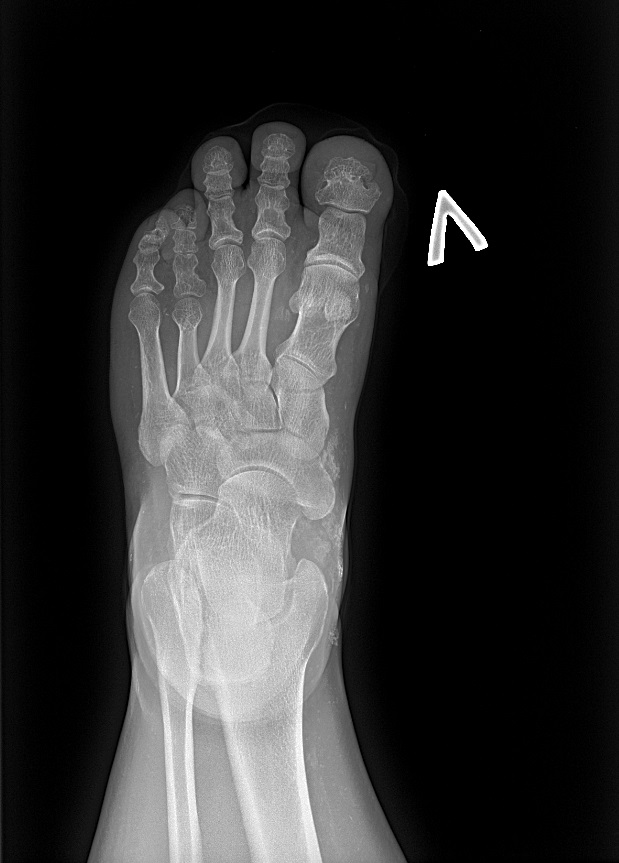

В ФГБУ НМИЦ эндокринологии наблюдается женщина 35 лет с ожирением, низкорослостью, депрессивными расстройствами, нарушениями кальций-фосфорного обмена, гипотиреозом. С 3 лет у пациентки отмечались тонические судороги на фоне фебрильной лихорадки и периодические миалгии. Впервые обследование проведено в 12 лет в связи с появлением карпопедальных спазмов, когда была выявлена гипокальциемия (Са общ. 1,3, при норме 2,0–2,6 ммоль/л), гиперфосфатемия (2,66 ммоль/л при норме 0,7–1,6) на фоне повышенного уровня ПТГ (268 пг/мл). Во время обследования в стационаре также впервые обратили внимание на особенности фенотипа: у девочки отмечалось ожирение, укорочение IV и V пястных и плюсневых костей (рис. 1, 2), пальпировались плотные подкожные образования, не спаянные с окружающей тканью, безболезненные. Гистологическое исследование биоптата образований доказало наличие подкожных кальцификатов с распространением в перимизий. По данным мультиспиральной компьютерной томографии (МСКТ) головы выявлено обызвествление базальных ядер и субкортикальных отделов головного мозга (рис. 3). Был установлен диагноз «псевдогипопаратиреоз Iа типа». Молекулярно-генетическое исследование подтвердило наличие мутации в гене GNAS – гетерозиготная мутация GNAS в сайте сплайсинга с.585+2Т>С. По поводу резистентности к ПТГ назначен альфакальцидол, в последующем к терапии были добавлены препараты кальция. Прием препаратов осуществлялся под контролем показателей кальция крови с периодической коррекцией дозы. В 20 лет впервые выявлен субклинический гипотиреоз и назначена заместительная терапия препаратом левотироксина натрия с дальнейшей коррекцией дозы в зависимости от уровня ТТГ при контроле в динамике. Клинических признаков гипогонадизма не отмечалось: менархе в 12 лет, менструальный цикл регулярный. При сборе семейного анамнеза не было выявлено особенностей, указывающих на возможность наличия у родственников НОО или гипокальциемии: родители нормального роста, брахидактилии, подкожных образований у них не имеется, судорожных эпизодов или криптогенной эпилепсии ни у родителей, ни у ближайших родственников не отмечалось. У пациентки нет детей, но было 4 беременности, все окончившиеся абортами. Одна беременность – замершая, один аборт по желанию пациентки, 2 последние беременности были прерваны после получения результатов пренатальной диагностики, доказавшей наличие у плода той же мутации в гене GNAS, что и у матери.

Рис. 2. Брахидактилия: укорочение IV плюсневой кости слева.

В 35 лет пациентка поступила в НМИЦ эндокринологии с жалобами на судорожный синдром. При осмотре обращали на себя внимание низкорослость (рост 148 см), ожирение (87 кг, ИМТ 39) с лунообразным лицом, брахидактилия (рис. 4, 5), подкожные кальцинаты, положительный симптом Хвостека. При сжатии кистей в кулак отмечалась сглаженность в области IV–V пястно-фаланговых суставов – брахиметафалангизм (рис. 6). В ходе обследования была выявлена декомпенсация по кальций-фосфорному обмену и гипотиреозу: гипокальциемия (Са ион. 0,87 ммоль/л при норме 1,03–1,29), гиперфосфатемия (1,81 ммоль/л при норме 0,74–1,52), повышение уровня ПТГ до 136 пг/мл (15–65), гипотиреоз (ТТГ 7,37 мМЕ/л при норме 0,64–5,76, св.Т4 8,72 пмоль/л при норме 11,5–20,4) при нормальном уровне аутоантител (АТ) (АТ к тиреопероксидазе (ТПО) 1,77 МЕ/мл, при норме 0–5,6) и отсутствии эхо-признаков аутоиммунного тиреоидита по данным УЗИ щитовидной железы (рис. 7). В суточном анализе мочи гипокальциурия 0,804 ммоль/сут (2,5–8), 0,37 мг/кг/сут, гипофосфатурия – 12,52 ммоль/сут (13–42). Беседа с пациенткой выявила ряд психологических проблем, появление которых сама женщина связывала с тяжелым переживанием последнего аборта: на фоне депрессии перестала следить за питанием и регулярным приемом препаратов, отмечались прогрессирующий набор веса и периодическая боль в мышцах, развившаяся в итоге в карпопедальный спазм. Проявления острой гипокальциемии были купированы введением раствора кальция глюконата; показатели кальций-фосфорного обмена и функционального статуса щитовидной железы нормализовались после восстановления и коррекции приема альфакальцидола и левотироксина натрия. По поводу имеющейся депрессии получает антидепрессанты под наблюдением психоневролога.